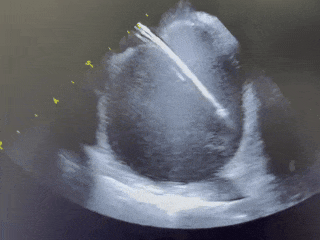

ICE下输送封堵器

MemoLefort封堵器展开后DSA下充分评估

肝位即刻造影,位置合适,上下缘无造影剂漏

牵拉试验,牵拉后有明显回弹,位置无移动

展开后DSA下造影,观察封堵左心耳开口无残余分流,且封堵器放置位置理想,充盈整个心耳开口处。肝位牵拉有回弹,无任何相关位移。